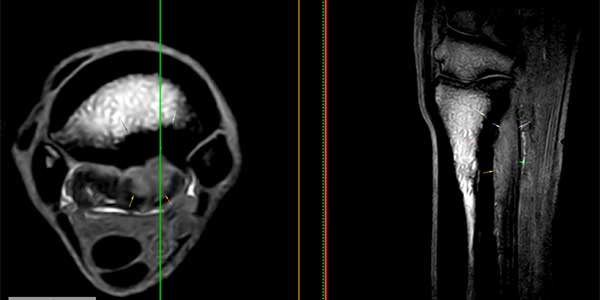

Het diagnosticeren van peesblessures gebeurt reeds 30-40 jaar aan de hand van een echografisch onderzoek. Deze diagnostische techniek is zeer geschikt op plaatsen waar de pezen oppervlakkig liggen. Voor diepere structuren zoals de bovenste aanhechting van de interosseus en de diepe buigpees in de voet bij het paard is een MRI scan de "technique of choice" om blessures en degeneratieve haarden goed in beeld te brengen. Ook toont de MRI-scan contrastrijk de actieve zones in de pees. (foto 3-7)

MRI beelden (vlnr STIR transversaal, GRE sagittaal, PD transversaal) van een hond met een chronisch degeneratieve aandoening van de carpus flexoren (m. Flexor Carpi Ulnaris) waarbij de pees ernstig verdikt is en een mix van heterogene intensiteiten vertoont.